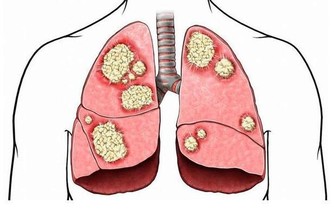

現在城市污染嚴重,霧霾多,多吃蘋果,可以增強我們的呼吸系統和心肺功能,減少煙塵對肺部的侵害。